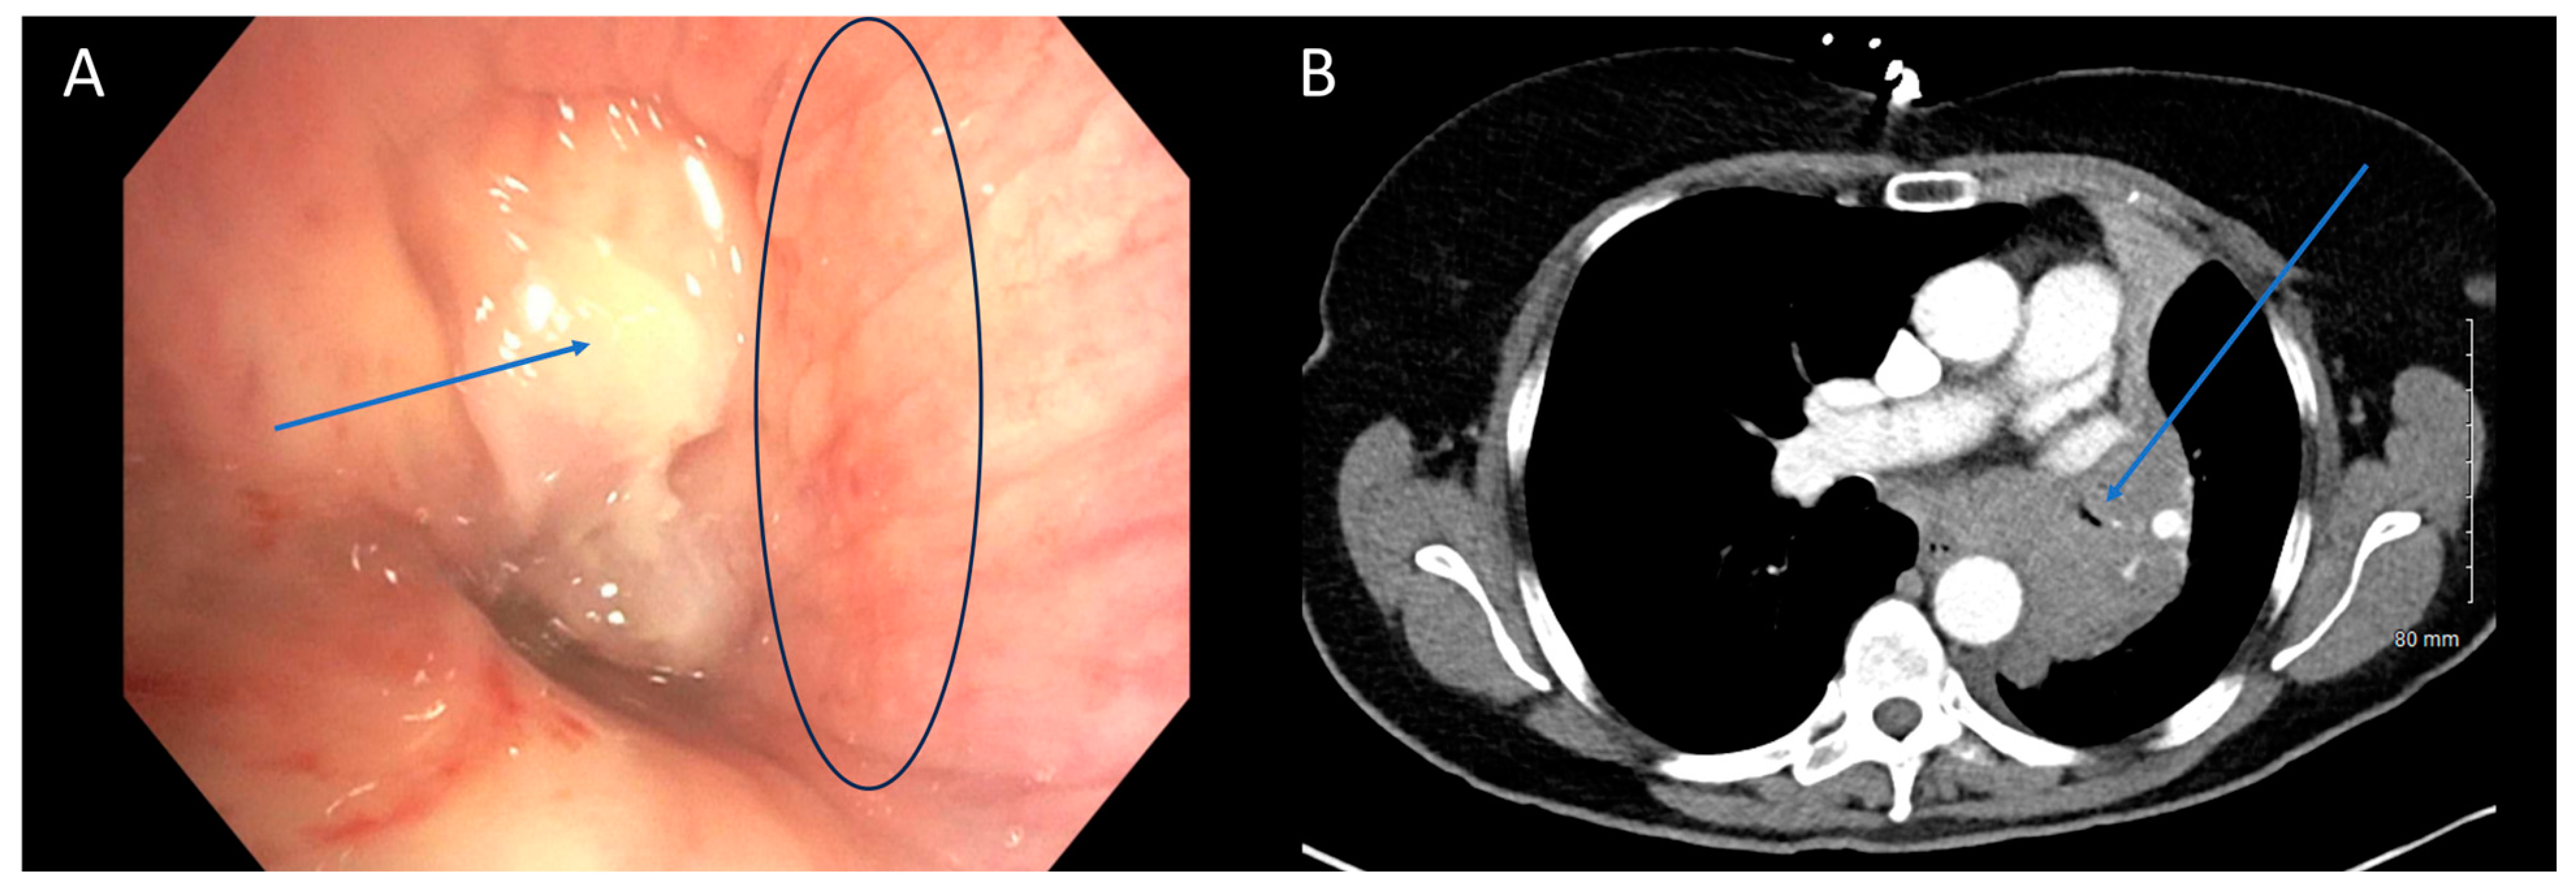

There was moderate agreement between bronchoscopy and CT in quantifying the degree of obstruction (65% agreement, Quadratic κ = 0.657, p < 0.001). Typically, when there was disagreement, it was between mild and moderate obstruction or moderate and severe obstruction. Few patients were categorized as having severe obstruction on CT (2/23, 9%) when mild obstruction was present on bronchoscopy, or mild obstruction on CT (1/61, 2%) when severe obstruction was present on bronchoscopy (Figure 1). In cases of moderate obstruction, CT tended to equally overestimate (7/19) and underestimate (7/19) the degree of obstruction. Several factors contribute to the discrepancy in the degree of obstruction between the two modalities. Bronchoscopists typically estimate the degree of obstruction visually, a subjective and variable method lacking standardization. The use of a fisheye lens in bronchoscopy may lead to an overestimation of obstruction severity, especially with variations in distance [20]. Jet ventilation, which may be used during rigid bronchoscopy lacks the ability to create significant positive end-expiratory pressure which could hold airways open more than positive pressure ventilation. This could result in a smaller airway caliber due to bulging of the posterior membrane. Additionally, the timing of the respiratory cycle during which the CT image is captured plays a role. Non-contrast CT scans are obtained during maximal inhalation, which may not accurately reflect conditions observed during therapeutic bronchoscopies. Contrast-enhanced CT scans obtained during maximal exhalation could better approximate the conditions encountered during bronchoscopy, although a direct comparison of the accuracy of the two methods has not been studied. In summary, imaging modalities introduce variability based on specific scan characteristics, while bronchoscopy introduces variability based on distance and visual estimation.

Figure 1. CT Underestimating Degree of Obstruction Compared to Bronchoscopy. Bronchoscopy (A) and CT (B) images depicting an endobronchial tumor in the distal trachea of a patient. The severity of obstruction appears to be greater when observed bronchoscopically compared to CT imaging. Arrows (in blue) highlight the tumors in the figure.